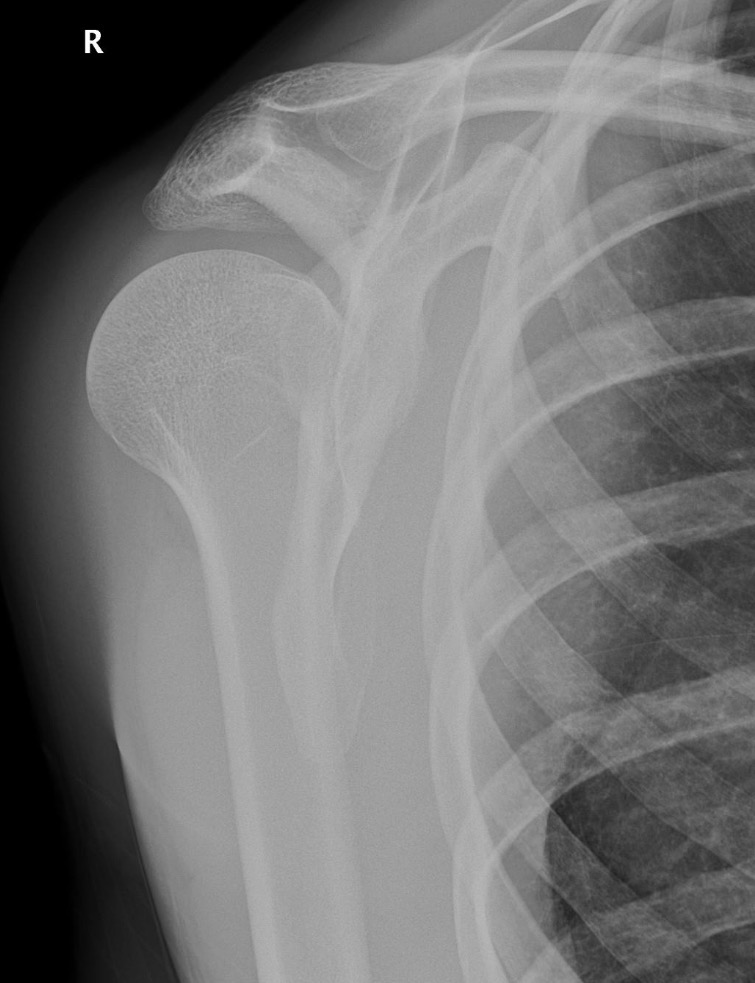

Bankart fracture/lesion

Hatchet Fracture

Hull-satch lesion